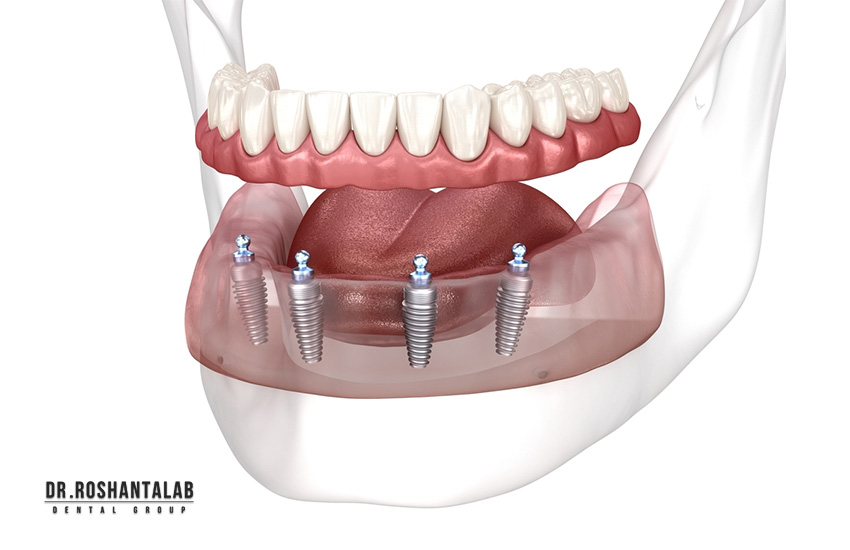

ایمپلنت کامل فک بالا و پایین یا فول آرچ ایمپلنت (Full Arch Implant Restoration)، روشی پیشرفته برای بازسازی تمام دندانهای یک فک یا هر دو فک است که برای سالمندان با بیدندانی کامل یا دندانهای آسیبدیده شدید طراحی شده. این روش شامل کاشت 4 تا 8 پایه ایمپلنت تیتانیومی در استخوان فک است و سپس پروتز ثابت یا نیمهمتحرک (مثل All-on-4، All-on-6 یا اوردنچر) روی آنها نصب میشود. برخلاف پروتزهای سنتی که لغزش دارند و نیاز به چسب، ایمپلنت کامل ثابت است و عملکرد طبیعی جویدن، صحبت کردن و لبخند را بازمیگرداند.

طبق American Dental Association (ADA)، ایمپلنت کامل فک بالا و پایین برای سالمندان بالای ۶۵ سال ایمن است و نرخ موفقیت ۹۵-۹۸٪ دارد، به شرطی که سلامت عمومی (مثل کنترل دیابت) رعایت شود. فک بالا معمولاً به 6-8 پایه نیاز دارد (به دلیل سینوسهای بزرگتر و تحلیل بیشتر استخوان)، در حالی که فک پایین با 4-6 پایه کافی است (استخوان متراکمتر).

۱. روش All-on-4 (۴ پایه برای هر فک)

در این روش، ۴ پایه تیتانیومی (۲ جلو، ۲ عقب زاویهدار) در هر فک کاشته میشود و پروتز ثابت ۱۲-۱۴ دندانی روی آن نصب میگردد. مناسب برای استخوان متوسط، جراحی در ۱ روز، بهبودی ۳-۶ ماه.

۲. روش All-on-6 (۶ پایه برای هر فک)

۶ پایه برای توزیع بهتر فشار، ایدهآل برای جویدن سنگین یا دندانقروچه. پروتز زیرکونیا مونولیتیک، دوام ۲۰+ سال.

۳. روش اوردنچر (Overdenture) روی ۲-۴ ایمپلنت

۲-۴ پایه و پروتز نیمهمتحرک با کلیک. ارزانترین، مناسب سالمندان با استخوان کم.